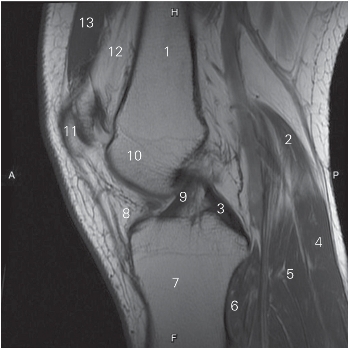

图5-26 经前后交叉韧带的矢状断层MR T1加权图像

1 股骨 femur 2 腓肠肌内侧头 medial head of gastrocnemius

3 后交叉韧带 posterior cruciate ligament

4 腓肠肌 gastrocnemius 5 比目鱼肌 soleus

6 腘肌 popliteus 7 胫骨 tibia

8 髌下脂肪垫 infrapatellar fat pad

9 前交叉韧带 anterior cruciate ligament

10 股骨外侧髁 lateral condyle of femur

11 髌骨 patella 12 股前脂体 prefemoral fat pad

13 股四头肌和肌腱 quadriceps femoris and tendon